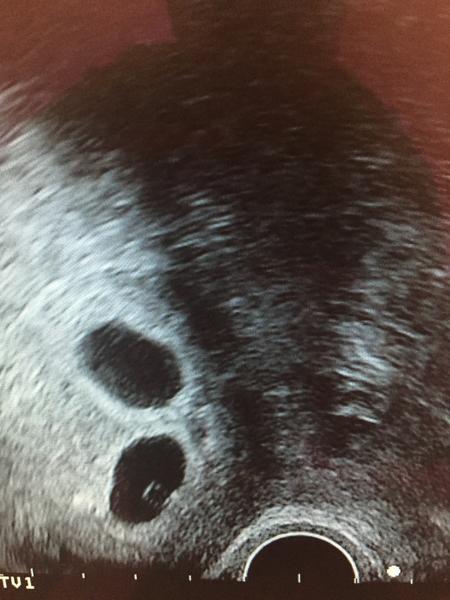

@lenna71 @ivancova @zuzankaa88 @michallll baby my silnieme, som prestastna a tak som sa bala ci tam dnes este nieco najdem 😀

@zuzankaa88 ano Zuzi dve...a baby pisu, ze to vyzera podla intenzity ciarky na 9 den na dvojky, haha zbohom zdravy rozum 😀 😀 😀